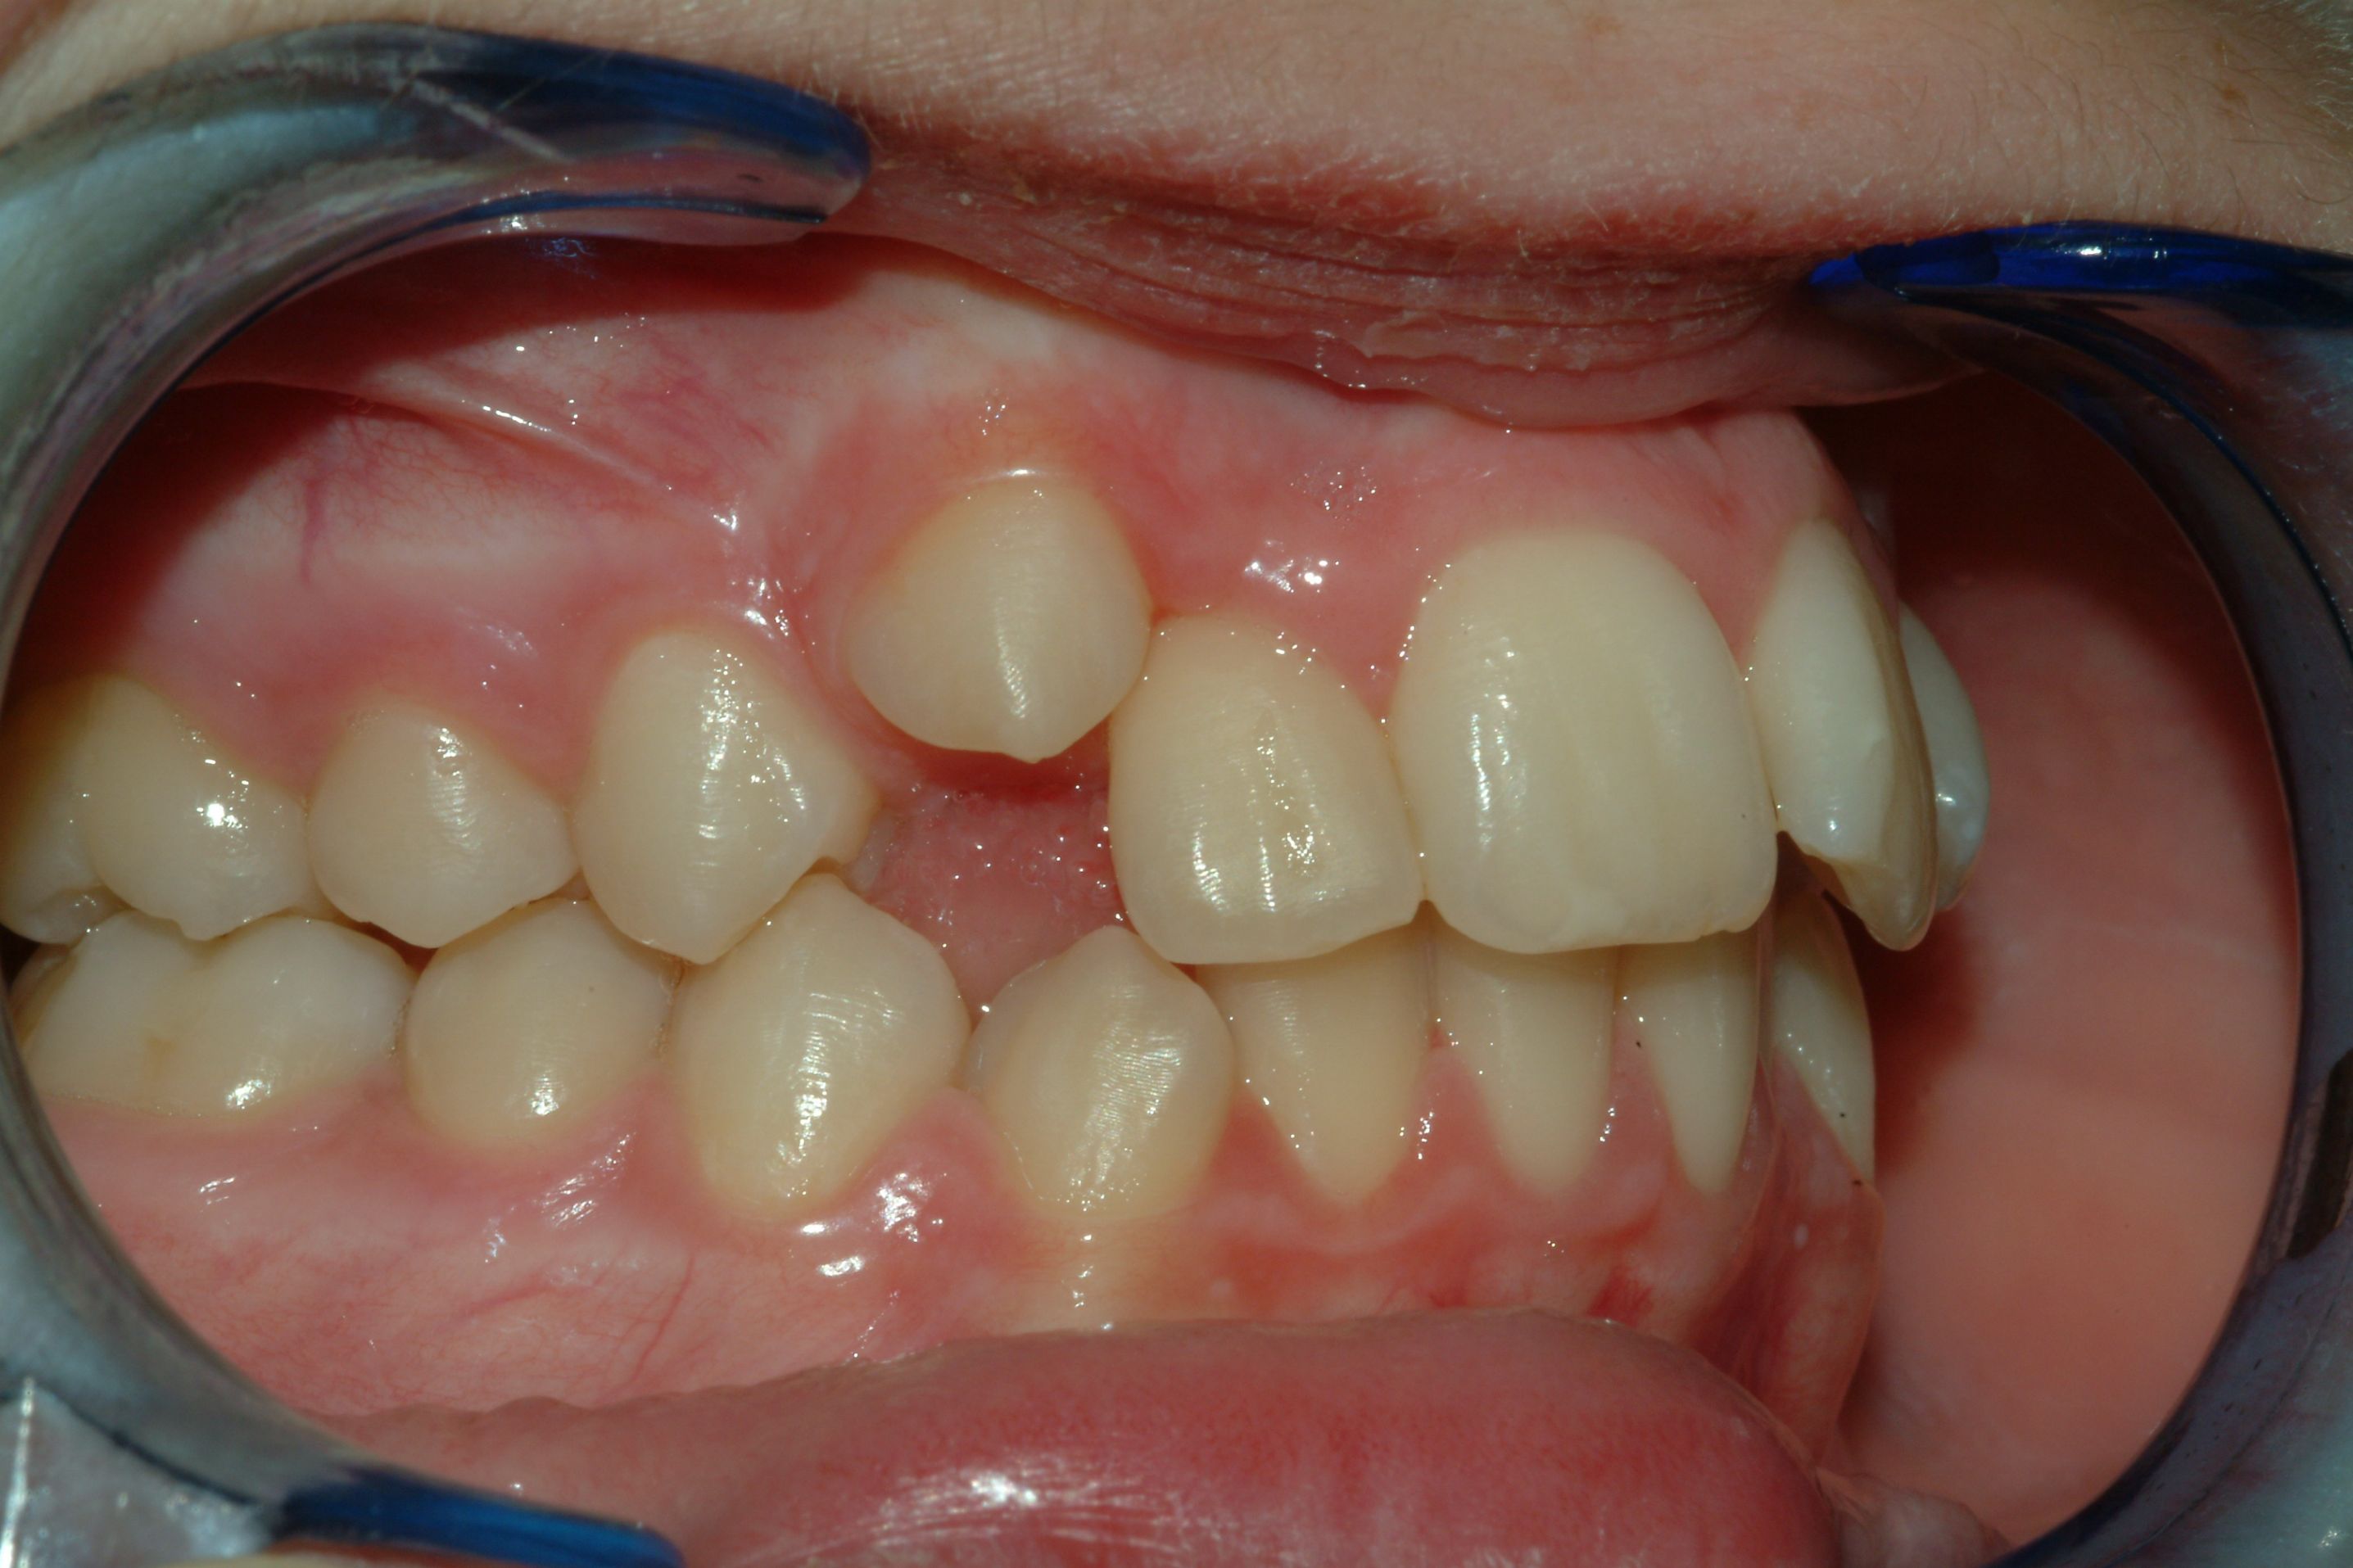

Le particolari caratteristiche dei bracket autoleganti interattivi consentono di diminuire l’attrito, in particolar modo nelle prime fasi di un trattamento ortodontico mantenendo la possibilità di un ottimale controllo della posizione tridimensionale degli elementi dentali.

Distinctive features of interactive self-ligating brackets allow to decrease friction particularly in the initial phases of orthodontic treatment, maintaining the possibility of an optimal control of 3D teeth position. The archwire sequence proposed by the Authors permits to make the most of Time2 brackets peculiarities, respecting in the same time biological needs of any specific malocclusion.